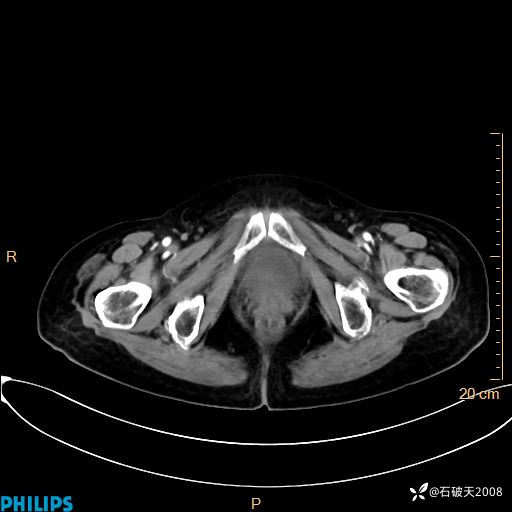

平扫